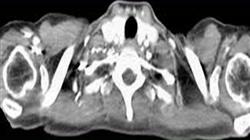

- Иконография клинических и диагностических изображений